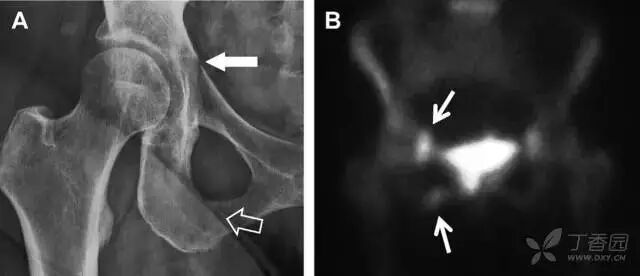

尽管仔细检查和评估,仍有一些外伤后髋部疼痛的患者,存在 X 片上难以发现的隐匿性髋部骨折。这种情况下,可以选择对骨髓水肿高度敏感的 MRI 进行随访(图 1)。

图 1 长跑运动员股骨隐匿性、应力性骨折。A 为髋部正位 片,虽未见明显骨折,但股骨颈基底部可见一模糊的线性硬化带(箭头)B 为 MRI 冠状位 STIR 序列扫描,示股骨颈应力侧可见一线性低密度信号影,周围包绕骨髓水肿的高密度影

从这个案例来看,长期运动的患者,如果出现髋部疼痛,X 线即使无特殊表现,也应考虑应力性骨折的可能性。

髋臼骨折

髋臼骨折最常见的类型是髋臼后壁骨折,几乎占髋关节骨折的 1/4,且常常合并髋关节后脱位。由于骨性结构重叠,可能肉眼看上去觉得非常轻微的骨折,事实却并非如此。髋臼后缘中断常常是髋臼后壁骨折的一个特征(图 2)。

图 2 为髋臼后壁骨折伴髋关节脱位患者。A 右侧髋关节 X 线片示股骨头后方可见一骨折线(箭头),髋臼后缘中断。B 左侧髋关节 X 片对照可见髋臼后缘连续(箭头)。C  CT 三维重建图像示髋臼后壁缺损,可见旋转、移位的骨折块(箭头)

耻骨骨折

具有持续损伤因素的耻骨支骨折,可能看似轻微,尤其是合并骨质疏松的患者。因此,特别需要注意皮质缺损和骨密度改变。长跑运动员易发生耻骨应力性骨折,常常发生在靠近耻骨联合的下支。由于这些骨折为非移位骨折,所以常常被忽视。

图 3 自行车事故患者,侧方受力的髋臼前柱/耻骨骨折。A 正位平片示右侧髂耻线轻微中断(实箭头),此处异常最初并未发现。此外,右下方其实还有一处轻微耻骨支骨折(空箭头)。B 10 天后行骨闪烁显像证实了髋臼前柱骨折和侧耻骨下支骨折(箭头)。值得注意的是,左侧前柱亦存在异常